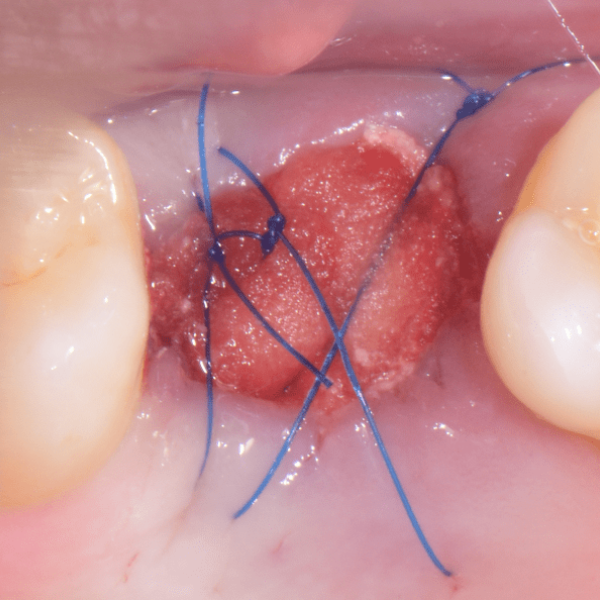

Tooth 14 slightly increased mobility, tenderness and bite pain. Suspected root fracture

Patient suffered from a root fracture. Needed removal and to restore hard and soft tissue.